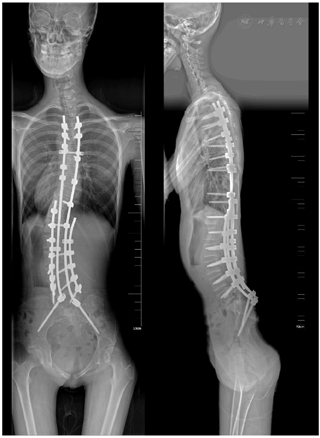

患者术后病情稳定,一般情况可,无特殊不适,神清,精神反应可,背部敷料在位干燥,伤口愈合良好,无红肿、渗出,X线示矫形效果满意,内固定位置良好。3个月后随访患者一般情况可,全脊柱X线示脊柱术后观,内固定在位,背部伤口已愈合,无特殊不适。

入院时患者一般情况可,精神反应可,心脏彩超、X线、肺功能等检查评估病情,排除手术禁忌症后,择期行后入路胸腰椎融合+后入路腰骶融合术对脊柱进行矫形,术中于T3-L5双侧按术前规划选择性植入椎弓根螺钉,双侧置入S2AI螺钉,透视确定螺钉位置良好后使用叠棒技术于腰弯凹侧置入短矫形棒一根并平移撑开矫形固定,再于短棒外侧安装长预弯矫形棒进一步撑开矫形固定,然后于腰弯凸侧放置矫形棒一根加压抱紧后拧紧固定,最后于近远端分别置于横联连接凹侧和凸侧矫形棒。术后予以预防抗炎、对症、支持治疗。术后患者复查CT示T10内固定左侧螺钉位置不良,再次行手术取出T10内固定左侧螺钉。待患者可自行站立后,复查全脊柱X线摄影示内固定位置良好(图4)。